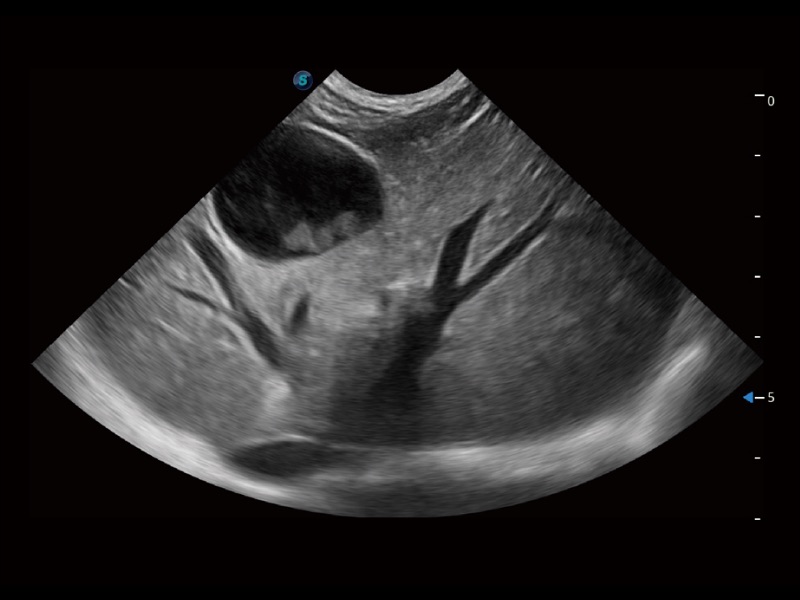

大型犬、马科、农场动物及大型异宠动物

通过创新的 Matrix E自适应滤波器和超长时间域算法,极大提升超低速微细血流的检出能力,同时更精准地滤除软组织和噪声信号,为兽用医生提供以往无法通过常规血流获得的疾病诊断信息。

通过色彩血流和实时宽景相结合,可观察到完整的静脉或动脉的血流,方便医生检查。实时扫查过程中,如有任何操作失误也可以很容易地进行回扫擦除,而不会中断扫查。

为精细结构及组织边缘提供高清晰度的图像和更大的成像视野。帮助减轻医生的用眼疲劳,快速精准获得测量的数据。